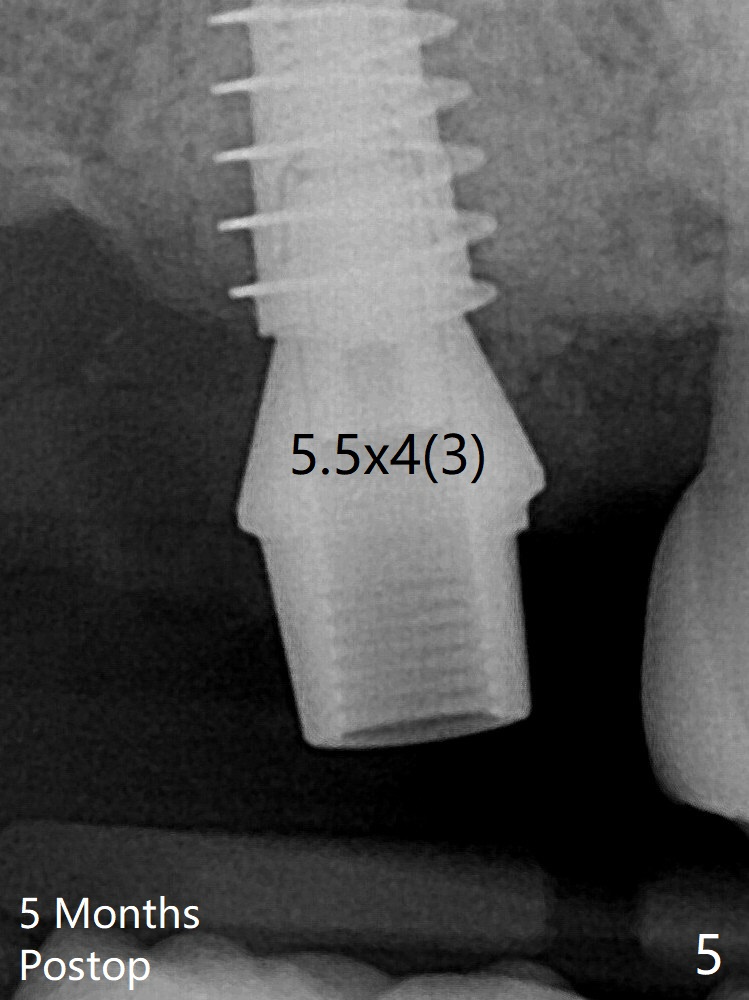

The implant threads are subcrestal 5 months postop (Fig.5).